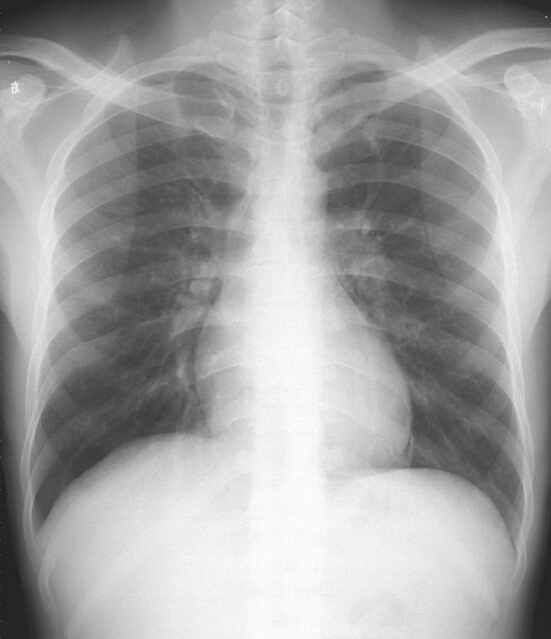

(图:王先生在来院治疗前的检查显示脊柱有轻度变形)

(图:王先生在治疗后的检查结果显示脊柱变形已改善)